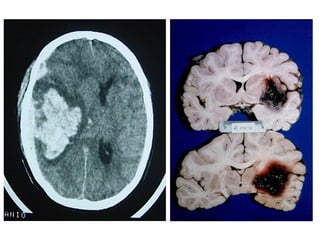

Tomografia Computadorizada do Crânio

• Alto grau de confiabilidade;

• Qualquer suspeita patológica envolvendo o encéfalo é indicativo de

TC;

Alterações visualizadas:

   Neoplasias;

   Lesões;

   Tumores

   Metástases;

   Hemorragia intracraniana;

   Aneurisma;

   Abscesso;

   Atrofia cerebral;

   Alterações pós-traumáticas;

   Alterações congênitas.